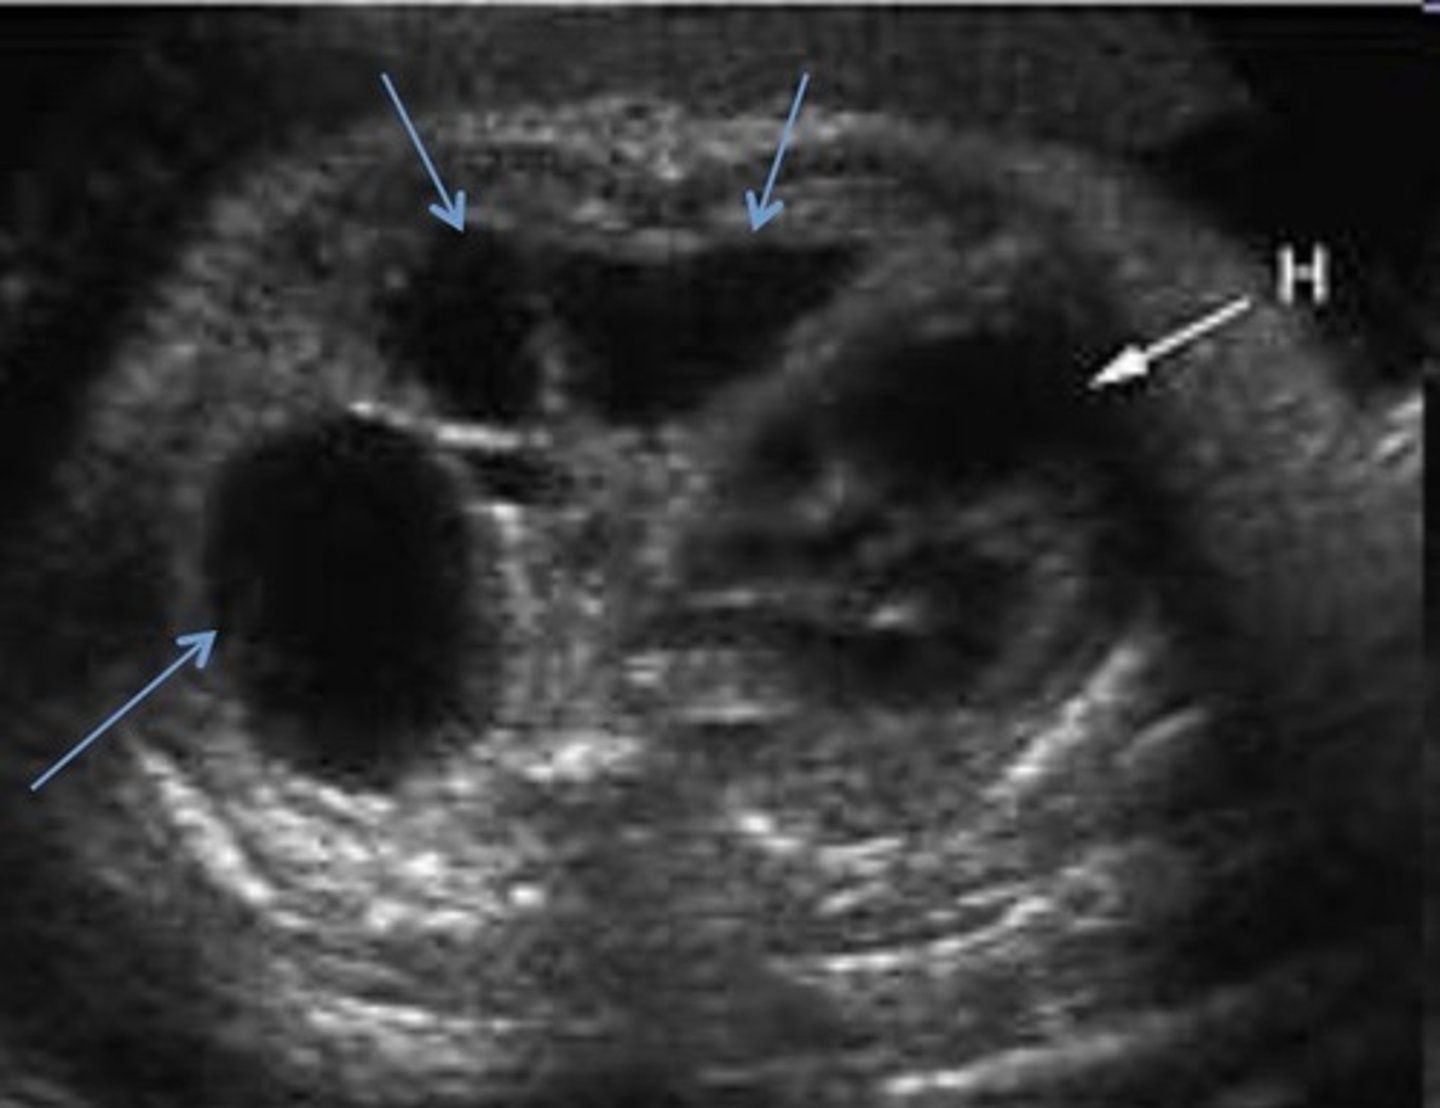

Dandy-Walker Malformation

Defect in vermis of cerebellum that dilates the 4th ventricle

Splaying of cerebral hemispheres - enlarged cisterna magna